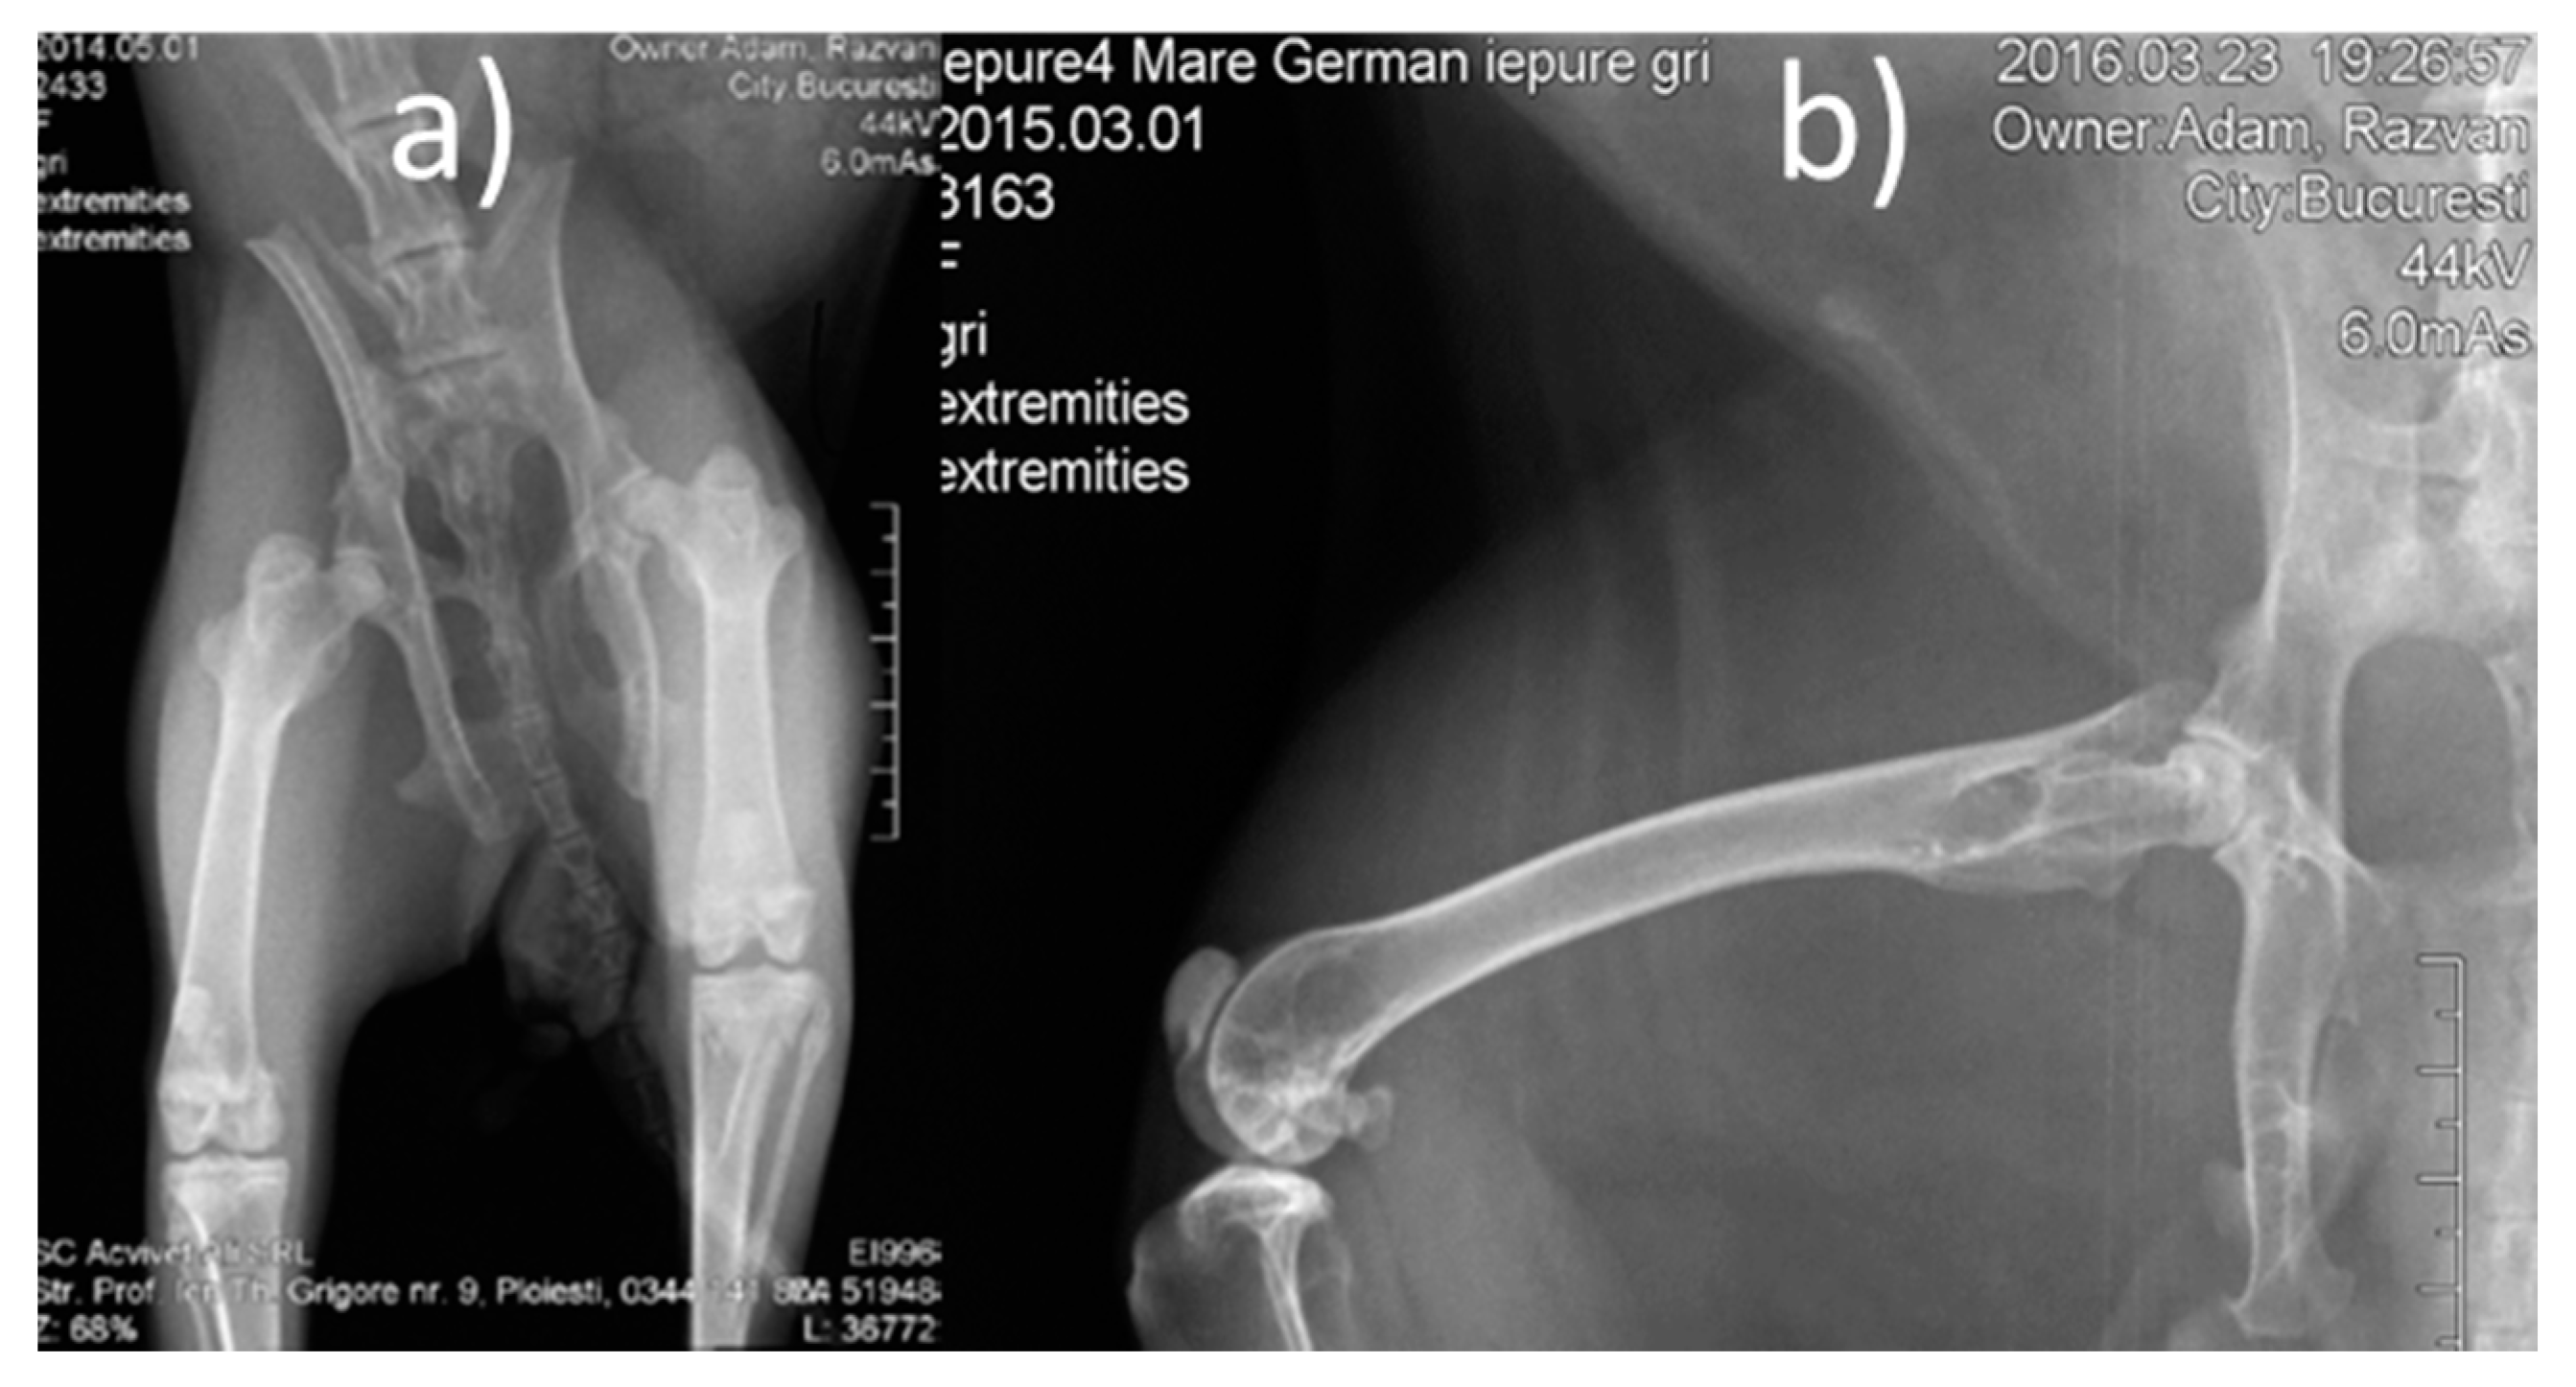

Pre-operative procedures: Lower limb radiographs were made, in two incidents, anterior-posterior and laterally (Figure 3). The animals were dewormed using Ivermectin, at a dose of 0.1 mL/kgC, subcutaneously (SC). Pre-operative antibiotic therapy was used (one dose of Enrofloxacin (Boytril 5%) at a dose of 10 mg/kgC, subcutaneously).

Figure 3.

Pre-operative X-ray images (a) front view, (b) lateral view.